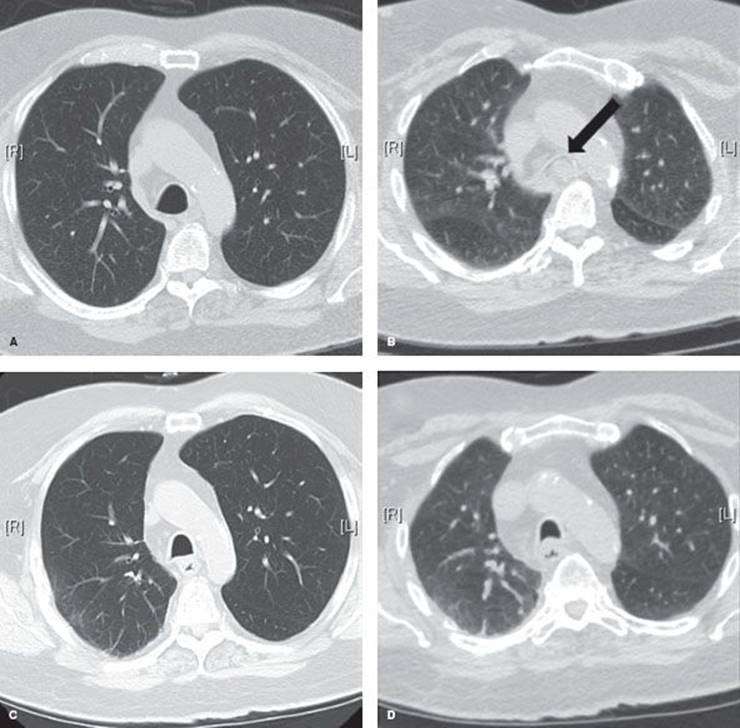

Establishing a diagnosis of tracheomalacia can be accomplished with dynamic airway computed tomography (CT) or functional bronchoscopy. Dynamic airway CT scanning has been shown to reliably identify airway collapse. The protocol for this involves scanning during a breath hold at total lung capacity and comparing the luminal patency to another series, which is obtained during a forced expiratory maneuver. The airway cross-sectional area is obtained by hand tracing the inner wall of the airway’s contour with an electronic tracing tool, and then the percentage of expiratory luminal collapse can be calculated (Fig. 40.1). Functional bronchoscopy involves fiberoptic endoscopy of the awake patient. Similar coached expiratory maneuvers are performed to estimate the degree of luminal collapse (Fig. 40.2). Concordance between these two diagnostic methods has been demonstrated. Nevertheless, both studies are utilized to assure that severe tracheomalacia is present. Air trapping, emphysema, or other parenchymal abnormalities may be detected additionally with CT scanning. Bronchoscopy may detect endobronchial abnormalities such as diverticula, tumor, or inflammation that might be missed radiographically.

Figure 40.1 Dynamic airway CT images. A: Preoperative end-inspiration at distal trachea. B: Preoperative dynamic expiration at distal trachea. Arrow points to 100% collapsed airway lumen. C: Posttracheoplasty end-inspiration image at distal trachea. D: Posttracheoplasty dynamic expiration image at distal trachea.

Assessment of the results of tracheoplasty should be performed 3 months postoperatively, including dynamic airway CT and functional bronchoscopy (Fig. 40.1).